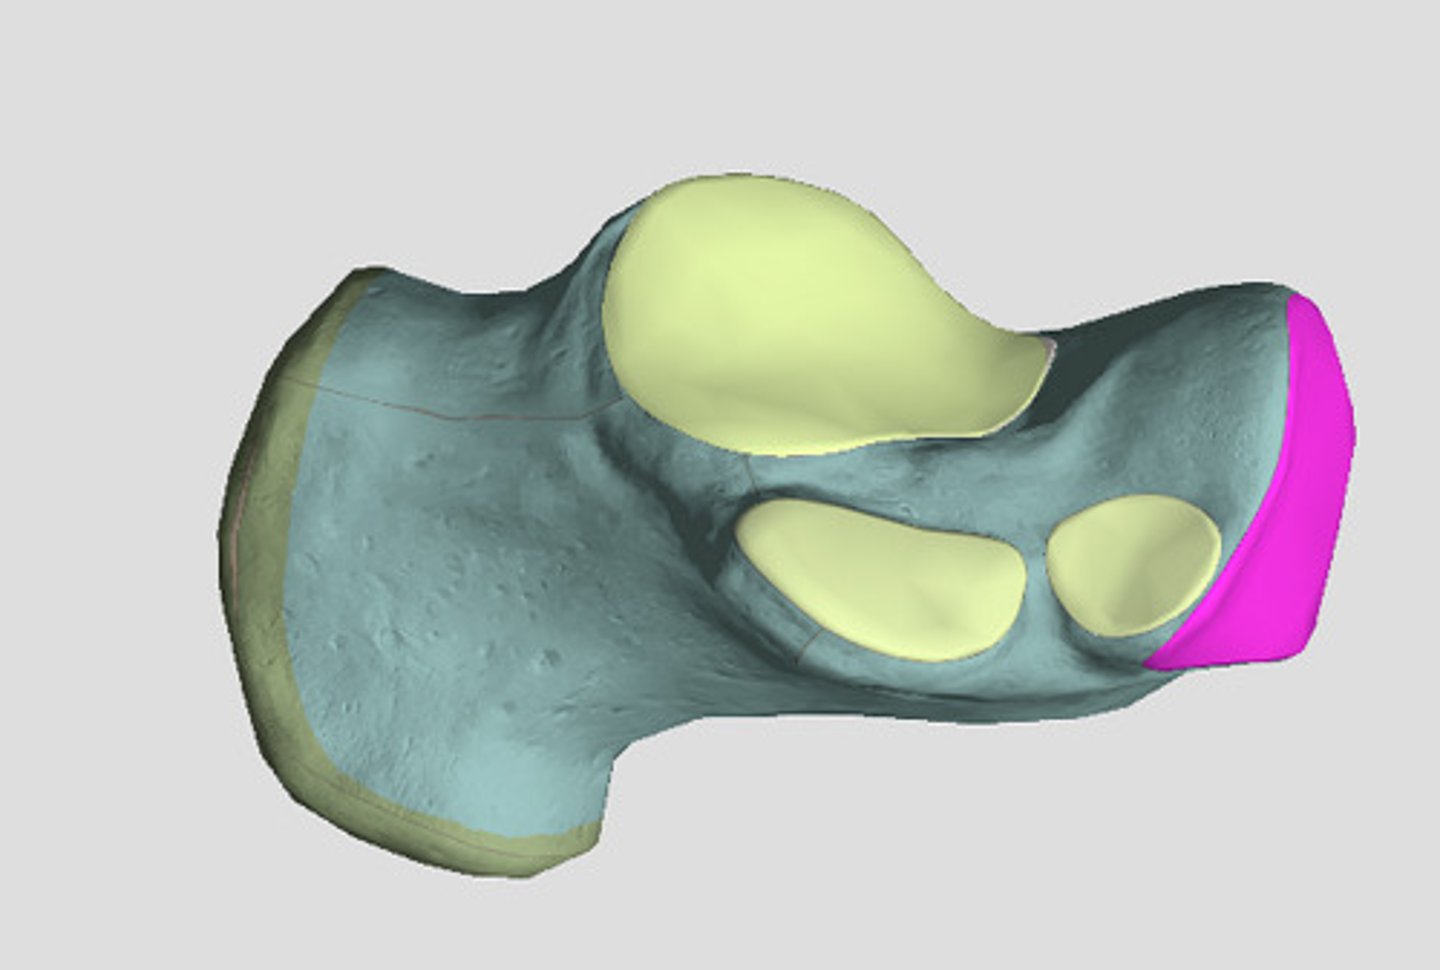

Patella

Apex

inferior surface for patellar ligament

Base

superior surface for quadriceps tendon

Medial articular surface (for medial condyle of femur; smaller)

green

Lateral articular surface (for lateral condyle of femur; bigger)

green